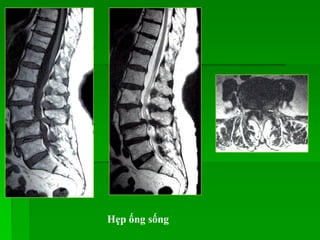

HẸP ỐNG SỐNG

 Nguyên nhân:

- Bẩm sinh: Hội chứng Morquio, hội chứng ngắn chân cung

- Mắc phải: Thoái hóa cột sống, lồi/thoát vị đĩa đệm, trượt

đốt sống, dày dây chằng vàng, phì đại mấu khớp…

Đường kính trước-sau bình thường của ống sống cổ # 10mm, ống

sống thắt lưng # 12-13mm.

Hẹp ống sống do TVĐĐ phía trƣớc, phì đại mấu

khớp và dày dây chằng vàng phía sau

HẸP ỐNG SỐNG Nguyên nhân: - Bẩm sinh: Hội chứng Morquio, hội chứng ngắn chân cung - Mắc phải: Thoái hóa cột sống, lồi/thoát vị đĩa đệm, trượt đốt sống, dày dây chằng vàng, phì đại mấu khớp… Đường kính trước-sau bình thường của ống sống cổ # 10mm, ống sống thắt lưng # 12-13mm.

Hẹp ống sốngdo TVĐĐ phía trƣớc, phì đại mấu khớp và dày dây chằng vàng phía sau